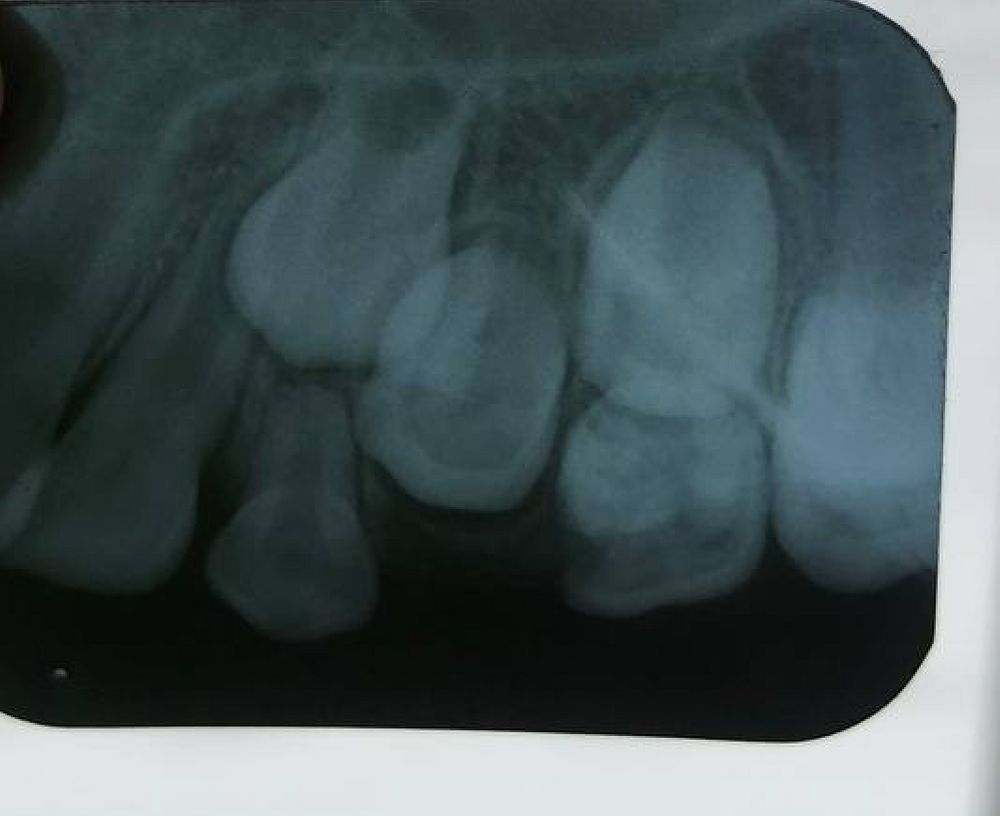

Сутра лор - посмотрела насморка уже и нет почти, я лечила, но что б исключить направила на рентген что б исключить гайморит, так как без этого идти к неврологу нет смысла. Но у него уже сильно до слез болел зуб, поэтому перед рентгеном пошли к стоматологу от тут же на этаже в соседнем кабинете, с острой болью его приняли без записи но подождать минут 20-30 пришлось, сидел плакал под кабинетом, я жалела. У стоматолога: дырка между 5 и 4 молочными, 5 лечить по возрасту вроде как можно, 4-й если лечить то только после рентгена, так как коренной может быть очень близко - тогда только рвать. Говорю - ок, у нас как раз и от лора направление на ренген все вместе сделаем. Нет - от лора можно здесь на первом этаже, а от стоматолога - только ехать в др место делать...ппц. Говорю - тогда 5-ку лечите, а 4-ку рвите, куда его вести если очень болят зубы. вышла жду под кабинетом, так как младшая тоже там нас ждет. Выходят - 4-ку вырвали, дырочка в ней была большая но корни все целые белые. Говорит я вас записала на 21-е пятерку лечить. Я - там сейчас временная пломба и лекарство? Стоматолог - нет, там сейчас ничего нет, мы же 4-ку вырвали там рана лечить пока нельзя надо что б зажило. Немая сцена. Сказать что я оху..а(перечеркнуто) удивилась, ничего не сказать. Ведь можно было полечить 5-ку, а потом вырвать 4-ку, что мешало? ну ладно, как выяснилось на следующий день, хорошо что 5-ку мы не лечили и не сврлили - ее тоже только рвать или ждать пока выпадет сама.

Утром проснулся - напухла щека, темпа 37+. Везу к стоматологу с утра. Привезла и показываю, говорю - нам наверно не к вам а к стоматологу хирургу, дайте пожалуйста направление. Она посмотрела - давайте сначала на рентген. Выписала направление, съездили сделали, вернулись. Она смотрит - у вас с лункой все хорошо, не знаю почему так. Вот у вас правосторонний гайморит (зуб тоже справа рвали) наверно от него. Пошла с нашим ренгеном к лору. Обсуждали они чтото с лором потом позвали нас - посмотрели на ребенка. Лор - гайморит гной гонит не в щеку, а наоборот внутрь. Стоматолог - вот лунка от зуба тоже идеальная. Направляют нас в больницу в лор отделение в стационар ложиться. Я - в пятницу в стационар? там чтото разве делать будут на выходных? мне просто сейчас нужно ребенка пролечить что б у него щеку не раздуло еще больше, может нам к стоматологу-хирургу?